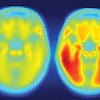

A Genetic Variant Could Radically Change Our Thinking on Alzheimer's Researchers have identified a new link between Alzheimer's and a protein called tau that could help treat the disease in the future.

Multi-gene test found effective in predicting Alzheimer's disease SAN FRANCISCO, Sept. 23 (Xinhua) -- A research team has found that a new test combining the effects of more than two dozen genetic variants does a better job of predicting which cognitively normal older adults will go on to develop Alzheimer's dementia.